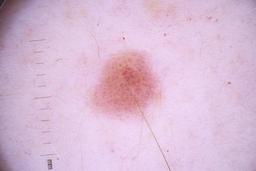

ISIC_4077341

- Challenge 2020: Training

Clinical

| Field | Value |

|---|---|

| acquisition_day | 1 |

| age_approx | 50 |

| anatom_site_1 | Trunk |

| anatom_site_2 | Anterior trunk |

| concomitant_biopsy | False |

| dermoscopic_type | contact non-polarized |

| diagnosis_1 | Benign |

| diagnosis_confirm_type | serial imaging showing no change |

| family_hx_mm | False |

| image_type | dermoscopic |

| lesion_id | IL_9238622 |

| patient_id | IP_1969685 |

| personal_hx_mm | True |

| sex | male |